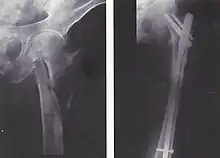

Haste intramedular

Para fraturas da diáfise, a redução e haste intramedular são recomendados atualmente. O osso é realinhado, e em seguida uma haste de metal é fixada atravessando a medula óssea. A haste é estabilizada com pregos em cada extremidade. Este método oferece menos exposição, 98% de consolidação, menores taxas de infecção (1%-2%) e menos cicatrizes.[13]